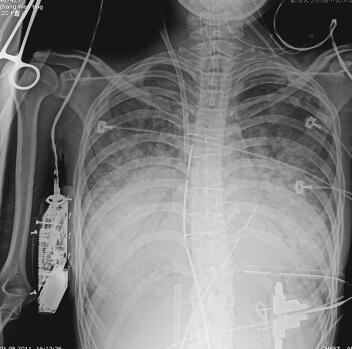

第二阶段(入院后第7~26天):二尖瓣置换术后患者心功能明显改善,多次复查心脏超声均提示心脏舒张及收缩功能未见明显异常,瓣膜功能良好。但患者感染难以控制,考虑感染源:①肺部感染:无法脱离ECMO,胸片提示双肺渗出影(图1),多次痰培养结果均提示鲍曼不动杆菌(MDR);②血源性感染:多次外周血及导管血培养提示洋葱伯克霍尔德菌;③感染性心内膜炎:考虑患者存在急性感染性心内膜炎,瓣膜赘生物形成,多为革兰阳性杆菌感染,但赘生物培养却未见细菌生长。鉴于以上感染相关证据,调整抗感染治疗方案为达托霉素和美罗培南联合左氧氟沙星,并加强气道管理,入院24天后病情明显好转,感染得到控制,逐渐增加呼吸机支持条件,并降低ECMO辅助条件,患者氧合及循环情况均未见恶化,复查胸片渗出较前吸收(图2~图4),故入院后第26天脱离ECMO,在常规机械通气的情况下,患者指脉氧饱和度可维持在95%左右,监测乳酸在1.0mmol/L左右,经皮氧分压88mmHg,经皮二氧化碳分压50mmHg。

图1 开始ECMO胸片